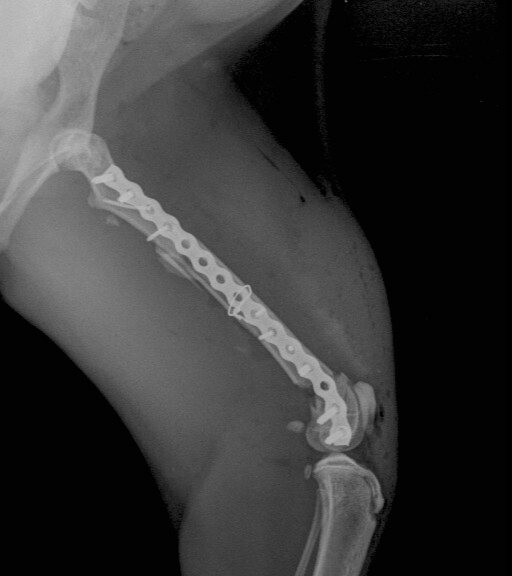

Botbreuken herstellen met platen van Synthes en kyon .

Specialisatie Patella luxatie ( losse knie)  kruisband herstel bij hond en correctieve osteotomies , kunstgroeve, kunstknie bij hond en kat .